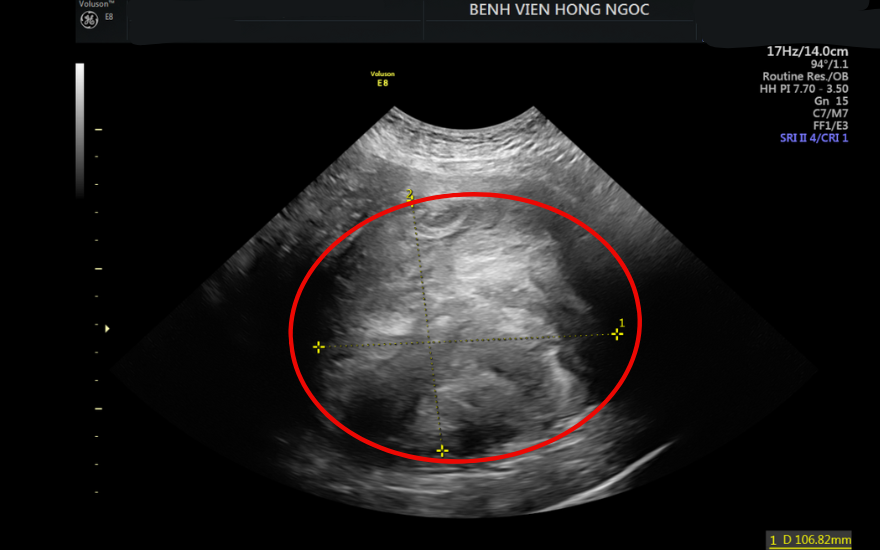

Khối u kích thước hơn 10cm cắm sâu trong cơ tử cung

Sau hơn 3 tiếng cẩn thận trong từng thao tác, ê-kíp phẫu thuật đã loại bỏ thành công khối u nặng hơn 1,4kg và toàn bộ tử cung, bệnh nhân không cần phải truyền máu trong và sau mổ.